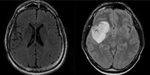

Investigated advanced neural network architectures, including Vision Transformers (ViT) and CNNs, for Cerebral Arterial Stroke Imaging. Applied transfer learning and fine-tuning techniques on pre-trained models for improved feature extraction, enhancing diagnostic precision. Implemented ensemble learning methods to combine model predictions and utilized cross-validation techniques to ensure robustness and generalizability in prognostic outcomes.